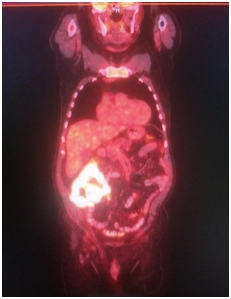

Выполнено ПЭТ/КТ исследование с 18F-ФДГ.

Выявлен гиперметаболический опухолевый процесс в области слепой и восходящей ободочной кишки (SUVmax 21,9), окружающая параколитическая клетчатка неравномерно инфильтрирована, с небольшим количеством жидкостного содержимого. Просвет кишки неравномерно сужен. В окружающей параколитической клетчатке, брыжейке тонкой кишки, отмечаются лимфоузлы,  размерами до 6-8 мм по КО, с умеренным накоплением РФП, SUVmax 4,3.

IMG_4389-27-09-18-09-40.JPG IMG_4389-27-09-18-09-40.JPG IMG_4389-27-09-18-09-40.JPG IMG_4389-27-09-18-09-40.JPG